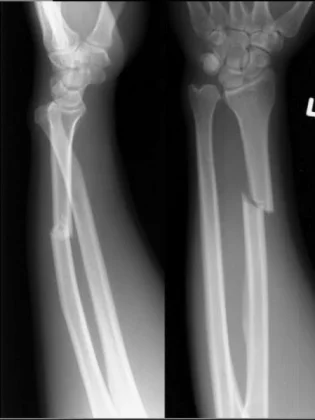

Galeazzi Fracture/ Dislocation

Fracture of the radius with dislocation of the distal radio-ulnar joint

“Fracture of necessity”

- Necessitates surgery

“Fracture of necessity”:

- Plating of radius

- Reduction of distal radio-ulnar joint (+/- Fixation)